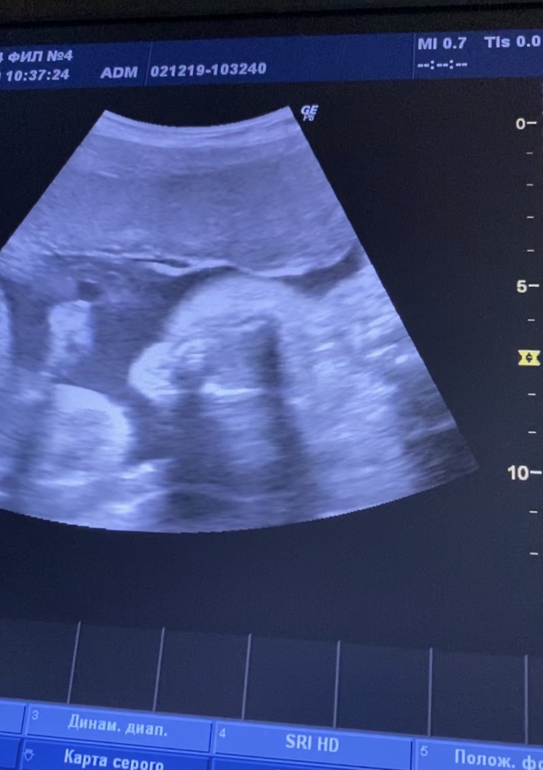

Узи 28 недель

Всё о нашей беременностиВот и прошло мое крайнее узи перед декретным отпуском. Уже пролетело 28 недель. До встречи осталось не долго. Нам наконец-то подтвердили пол уже все хорошенько видно 🤣 ждём девочек 👧🏼 Захотелось пойти накупить бантиков 😂 По показателям все отлично. Шейка 38, малышки по 1200 грамм. Но вот нижняя уселась на попку. Теперь переживаю успеет ли перевернуться. Буду надеяться на лучшее. Впереди самое сложное: выбор имён 😂 Совсем не верится, что осталось так мало времени, так хочется подольше насладиться этим положением (надеюсь мнение не изменится 🤣). Ну и напоследок мои курносики ❤️